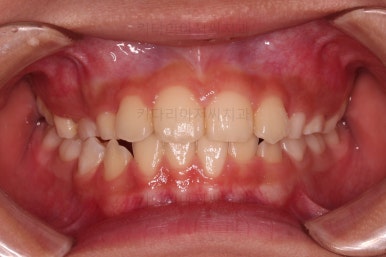

Case 2. 전/후

CASE 2.

나이 : 8세

총 치료기간 : 2주(2달 아님, 2주 맞음)

마찬가지로 얼굴모습 부터 분석해요.

골격에 문제가 있는 진짜 주걱턱은 아니라고 판단이 되었어요.

대신 앞니가 거꾸로 물려있어 웃는 모습부터 드러나는 치열의 모습까지 부자연스러운 모습인데요.

이번 환자분도 치료가 굉장히 빨리 끝났어요.

2주만에 해결!

장치도 굉장히 심플하고, 비용도 매우매우 저렴하답니다.

같은 문제를 고급 장치를 이용해서 비싸게 치료할 수도 있지만 목표치가 적당하다면 매우 좋은 치료라고 생각합니다.

바로 부산어린이교정 전후사진 비교해 볼게요.

단, 2주만에 문제시 되는 딱 한 개의 치아에만 포커스를 맞춰 해당 치아 반대교합만 개선해준 매우 훌륭한 치료였습니다.